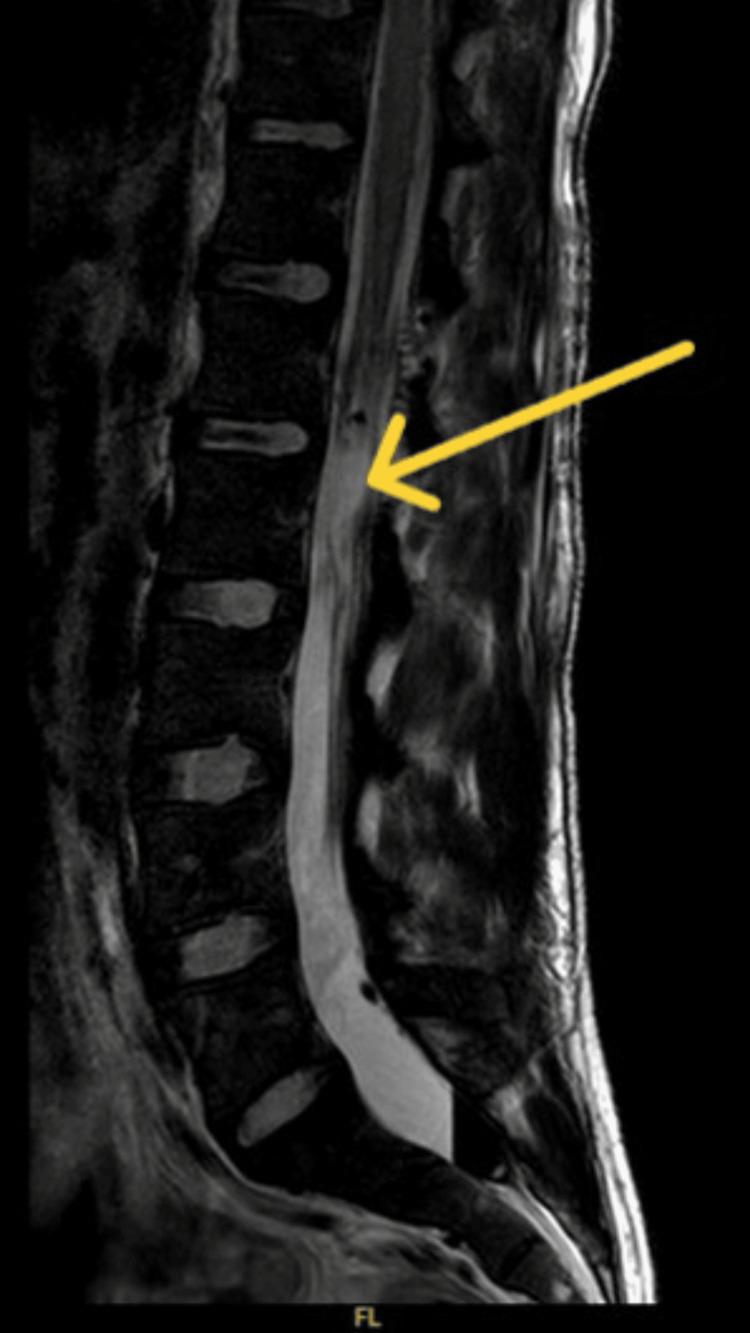

Myxopapillary ependymoma (MPE) is a rare, slow-growing tumor that commonly arises in the lumbosacral region of the spinal cord, within the filum terminale and cauda equina. The frequent presentation of MPE is back, sacral, or leg pain. The tumor's size, site, and extension usually influence these symptoms. MPE is usually evaluated using magnetic resonance imaging (MRI) because of its superior soft tissue contrast. The best treatment modality is total surgical resection, which improves the long-term survival rate, with follow-up imaging recommended to ensure total resolution. Here, we present the case of a 29-year-old male who presented with symptoms suggestive of severe neurological impairment. An MRI scan revealed an intradural lesion arising from the cauda equina with peripheral and intrathecal haemorrhage, consistent with MPE. He was managed with laminectomy and microsurgical resection of the tumor, which achieved total resection. Postoperative follow-up found gradual improvement in his symptoms, and routine surveillance imaging confirmed the complete resolution of the tumor.

摘要

黏液乳头型室管膜瘤(MPE)是一种罕见的、生长缓慢的肿瘤,通常发生于脊髓腰骶段,终丝和马尾内。MPE的常见表现为背部、骶部或腿部疼痛。肿瘤的大小、位置和范围通常会影响这些症状。由于其软组织对比度优越,MPE通常采用磁共振成像(MRI)进行评估。最佳治疗方式是手术全切,这可提高长期生存率,建议进行随访成像以确保完全切除。在此,我们报告一例29岁男性病例,该患者出现提示严重神经功能障碍的症状。MRI扫描显示一个起源于马尾的硬膜内病变,伴有周围和鞘内出血,符合MPE。他接受了椎板切除术和肿瘤显微手术切除,实现了全切。术后随访发现其症状逐渐改善,常规监测成像证实肿瘤完全消退。